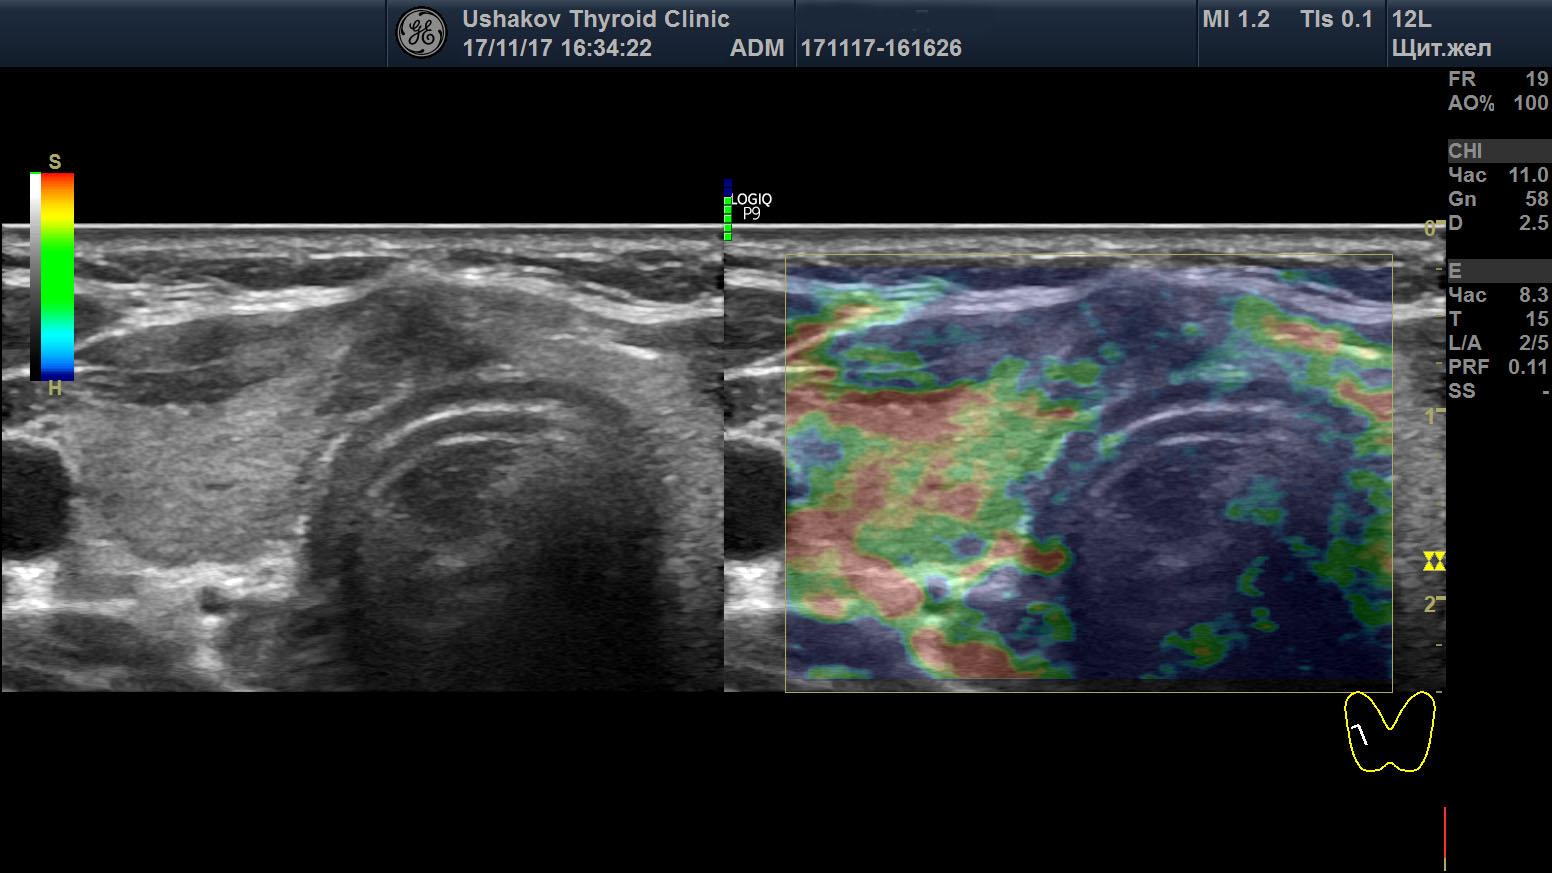

| Рисунок 1. В правой части перешейка щитовидной железы узел с признаками рака: 1) неправильная форма, вытянут не вдоль, а поперёк перешейка, 2) содержит значительно гипоэхогенную ткань, 3) граница узла в некоторых участках прерывистая. Класс по TI-RADS соответствует 4С. | | Рисунок 2. Этот же узел в режиме ЭДК. Кровоток узла значительной интенсивности с признаками неупорядоченности распределения сосудов. |

Рисунок 3. Этот же узел в режиме компрессионной эластографии. Значительно увеличена жесткость узловой ткани ― признак плотного расположения клеток в ткани узла (свойственно злокачественности).